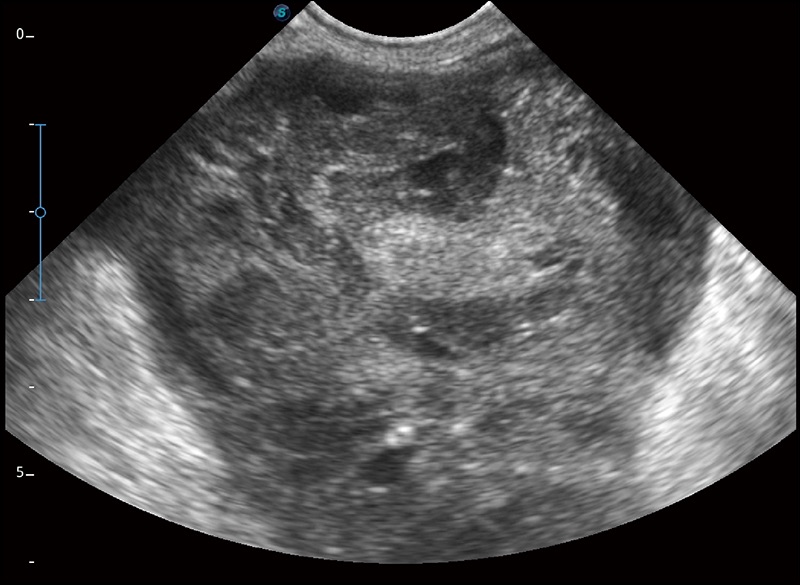

α1卓越的图像质量和便捷的工作流程,使每位宠物医生都能轻松扫查。其全面的兽用应用功能和紧凑型的结构设计,可以满足动物检查的多种需要。专业的预设检查模式和多领域测量软件包有助于为不同类型的动物提供检查, 让宠物医生能够出色的完成工作。

任意波束合成技术

在不牺牲时间分辨率的情况下提供出色的图像

空间复合成像

优化不同角度的图像

实时宽景成像

可实时观察感兴趣区域和病变位置